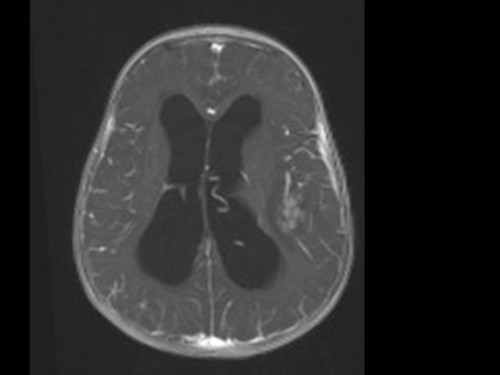

10 Monate altes Mädchen. Der Kinderarzt stellt fest, dass das kleine Mädchen einen recht großen Kopfumfang hat, nicht mit den Augen fixiert und anscheinend auch nicht richtig sehen kann. Damit bestätigt er die größten Befürchtungen der Eltern, denen in den letzten Wochen aufgefallen war, dass ihre Tochter nach keinem Spielzeug mehr greift und sie nur dann anlächelt, wenn sie zu ihr sprechen.

Bildgebung - MRT